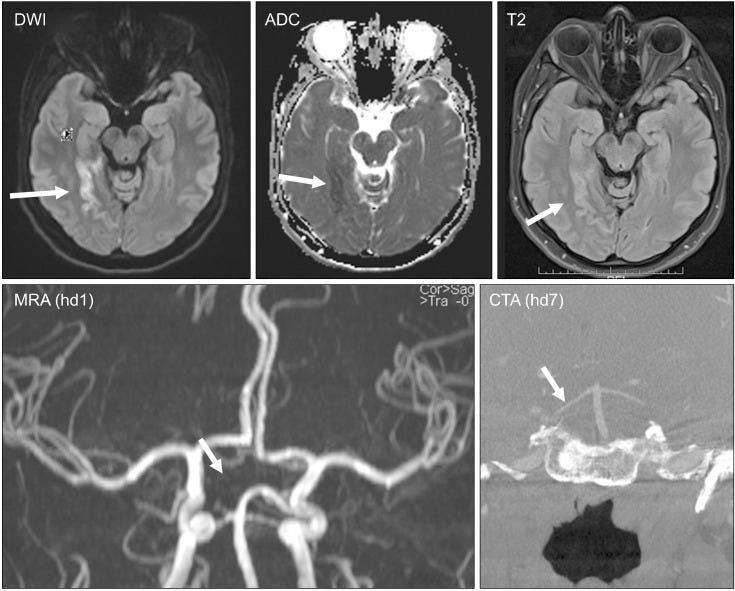

‘SARS-CoV-2 vaccines are not free of side effects and most commonly affect the central or peripheral nervous system (CNS, PNS).

…CNS disorders triggered by SARS-CoV-2 vaccines include headache, cerebro-vascular disorders (venous sinus thrombosis [VST], ischemic stroke, intracerebral hemorrhage, subarachnoid bleeding, reversible, cerebral vasoconstriction syndrome, vasculitis, pituitary apoplexy, Susac syndrome), inflammatory diseases (encephalitis, meningitis, demyelinating disorders, transverse myelitis), epilepsy, and a number of other rarely reported CNS conditions.

PNS disorders related to SARS-CoV-2 vaccines include neuropathy of cranial nerves, mono-/polyradiculitis (Guillain-Barre syndrome [GBS]), Parsonage-Turner syndrome (plexitis), small fiber neuropathy, myasthenia, myositis/dermatomyositis, rhabdomyolysis, and a number of other conditions.

The most common neurological side effects are facial palsy, intracerebral hemorrhage, VST, and GBS. The underlying pathophysiology is poorly understood, but several speculations have been generated to explain the development of CNS/PNS disease after SARS-CoV-2 vaccination.’